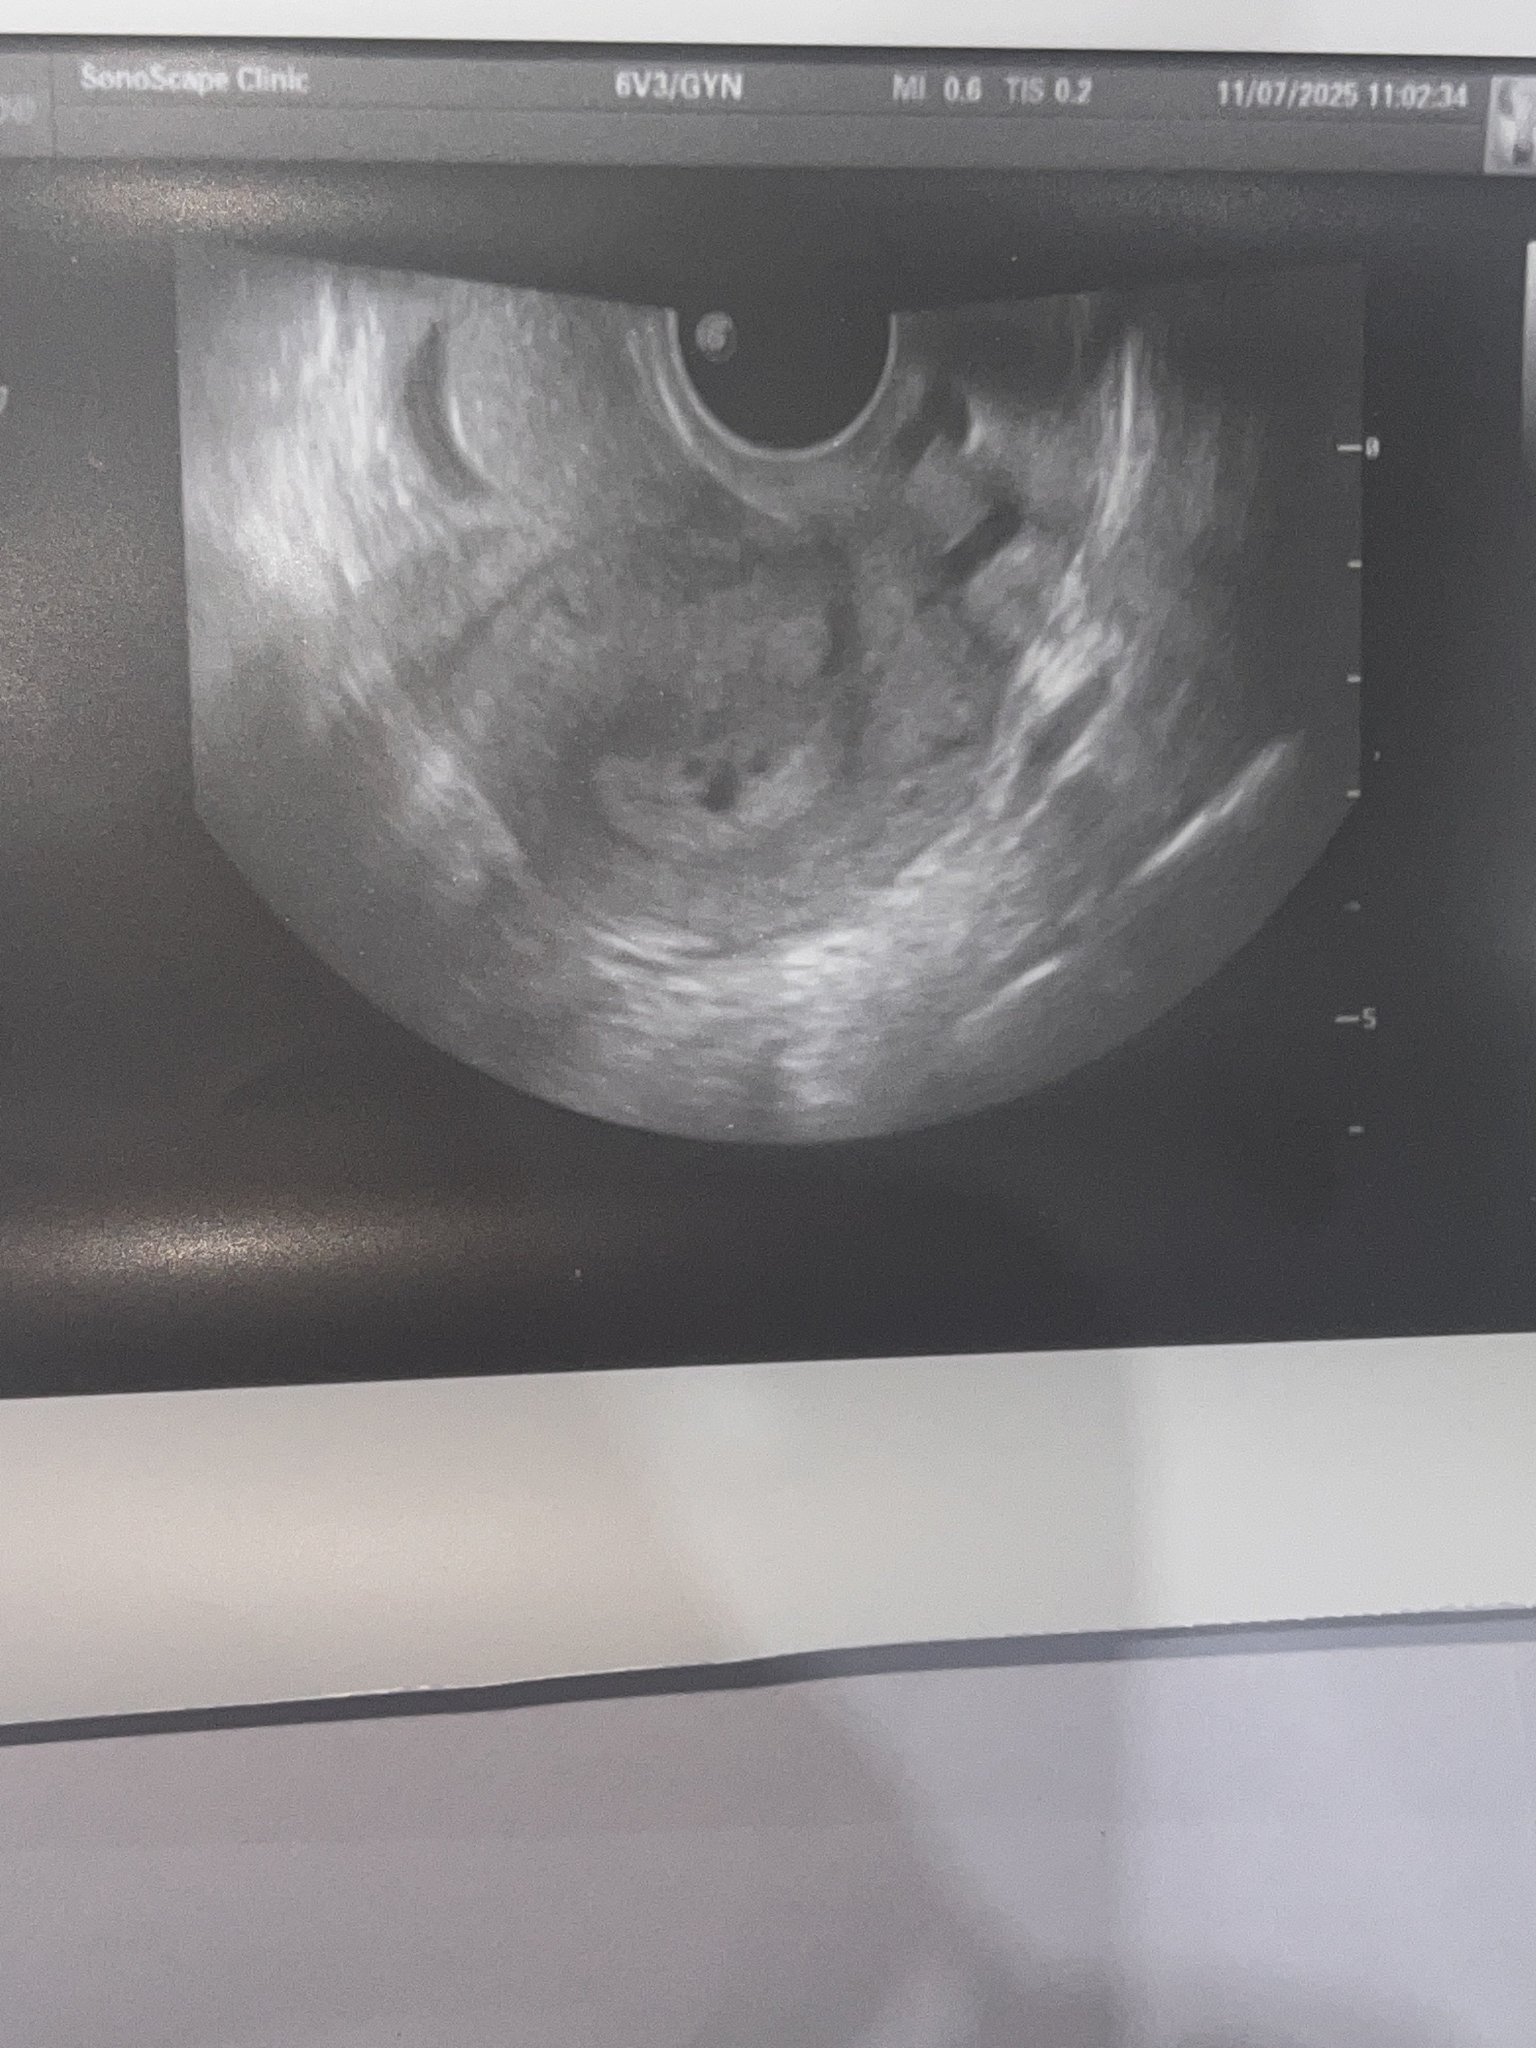

Днес бях на рутинен гинекологичен преглед

И АГ видя нещо приличащо на плоден сак и ме прати за кръвен тест който излезе отрицателен 0.100 IU както и предполагах понеже съм 11 след цикъл не мисля че е възможно тестове отрицателни а да се вижда на ехограф а и не правим опити за бебе в момента понеже лекувам бактерия

Мисълта ми е какво може да е това,опасно ли е на преглед съм отново след 2 седмици